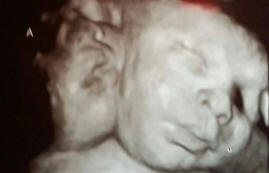

Takih otrok – enega na milijon, otrok ima dva sama delujoče glave, vendar eno telo in eno srce ter starši zelo vesel, da napolni družino.

Asa in Ali Hamley sta se rodila Robininim štiriindvajsetim staršem in Michelle. V medicini se njihov odklon imenuje dicefalični parapagus, torej stanje dvojčkov, ko so vsi organi zunaj razen ciljev imata skupno.

Ta primer je zanimiv, ker ponavadi takšni otroci ne preživijo. V enem od tisoč primerov lahko ženska zanosi s takim otrokom oz. vendar le en dvoglavi otrok na milijon navadnih otrok uspe preživeti.

Asa in Eli imata tri pljuča in z izjemo lahkomiselnih motnje v srcu, njihovo telo je v popolnem redu.

Zaradi dejstva, da so skoraj vsi organi in obtočni sistem dvojčka sama za dva, ne moreta se razdeliti, rešita življenje obema.